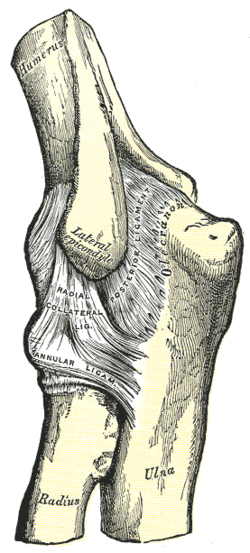

Left elbow joint, showing posterior and radial collateral ligaments. (Radial collateral ligament visible near center.) | |

The radial collateral ligament (RCL), lateral collateral ligament (LCL), or external lateral ligament[Explain 1] is a ligament in the elbow on the side of the radius.

The composition of the triangular ligamentous structure on the lateral side of the elbow varies widely between individuals[1] and can be considered either a single ligament,[2] in which case multiple distal attachments are generally mentioned and the annular ligament is described separately, or as several separate ligaments,[1] in which case parts of those ligaments are often described as indistinguishable from each other.

In the latter case, the ligaments are collectively referred to as the lateral collateral ligament complex (LCLC), consisting of four ligaments:[1]

- the radial collateral ligament [proper] (RCL), from the lateral epicondyle to the annular ligament deep to the common extensor tendon[1]

- the lateral ulnar collateral ligament (LUCL), from the lateral epicondyle to the supinator crest on the ulna. Near the attachment on the humerus this ligament is normally indistinguishable from the RCL and can be considered the posterior portion of it.[1] Martin 1958 described the distal part of the LUCL as "a definite bundle which normally crosses the annular band and gains attachment to the supinator crest, frequently to a special tubercle on that crest" but didn't name it.[3]

- the annular ligament (AL), from the posterior to the anterior margins of radial notch on the ulna, encircles the head of radius

- the accessory lateral collateral ligament (ALCL). from the inferior margin of the annular ligament to the supinator crest